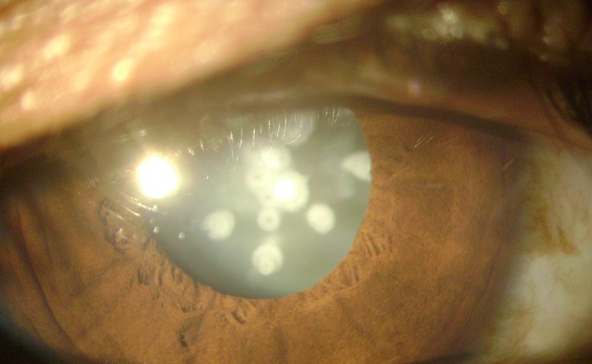

Un cas de cataracte céruléenne congénitale

Nous rapportons le cas d'un patient de 15 ans, qui consulte pour une baisse de l'acuité visuelle au niveau de l'oeil droit depuis 2 ans. A l'examen clinique, l'acuité visuelle est 1 /10. Le tonus oculaire est à 14 mmhg. L'examen du segment antérieur montre l'existence d'une cataracte faite d'opacités blanchâtres correspondant à une cataracte céruléenne congénitale. Le traitement a consisté en une cure de la cataracte par phacoémulsification avec une bonne évolution. La cataracte céruléenne est une forme de cataracte congénitale rare à teinte bleutée, faite d'opacités blanchâtres en couches concentriques avec en leur centre une disposition radiaire. L'acuité visuelle est assez bonne dans l'enfance mais peut se dégrader ultérieurement. Le gène de type 1 (CCA1) est en 17q24, le gène CRYBB2 de type 2 (CCA2) est en 22q. L'affection est autosomique dominante.